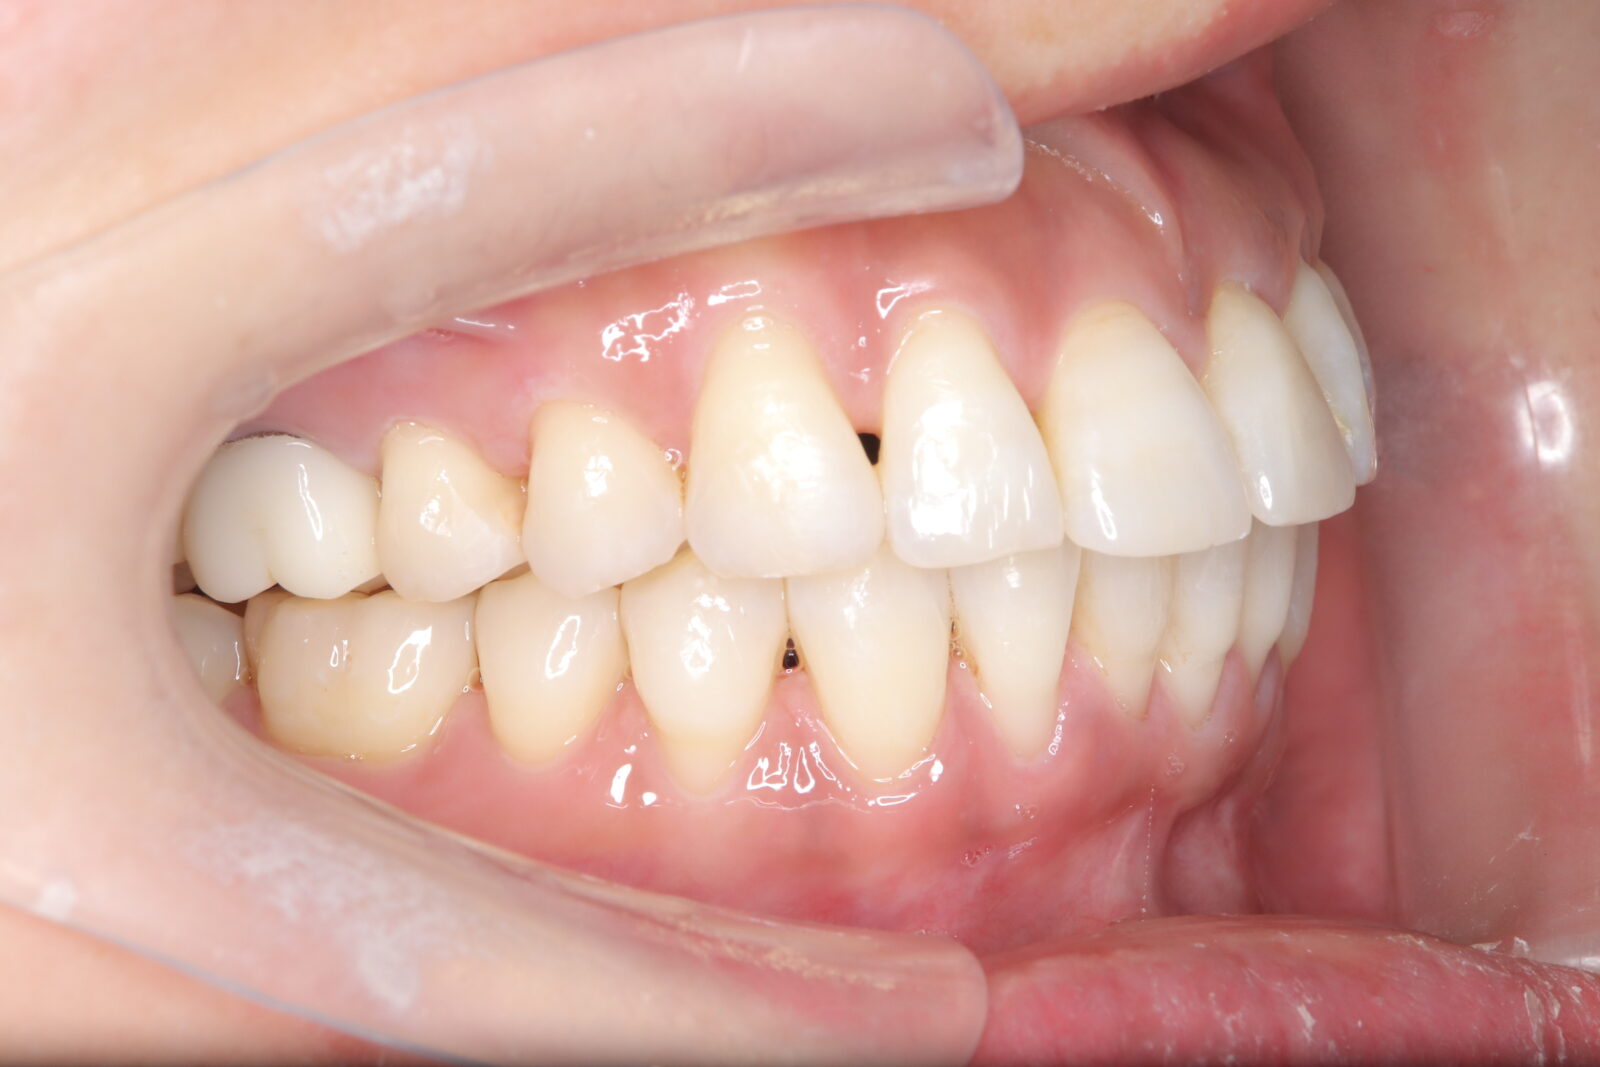

インビザライン(全体矯正)+ホワイトニングコースの症例

上下の前歯の歪みと奥歯のすれ違いをインビザライン(全体矯正)とホワイトニングで綺麗に矯正。

・費用:935,000円(税込)

・治療期間:30ヶ月

・通院回数:30回

・31歳女性

-リスクと副作用-

・長時間マウスピースを装着するため、むし歯や歯周病のリスクがある。治療後はリテーナーを装着しないと後戻りしてしまうリスクがある。

・ホワイトニング剤の影響で知覚過敏が起こる可能性がある。色が徐々に戻る可能性がる。